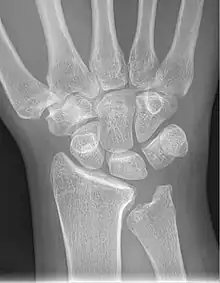

Left hand x-ray with Kienbock's Disease showing 4 mm negative ulnar variance and Kienbock's Disease Stage IIIB